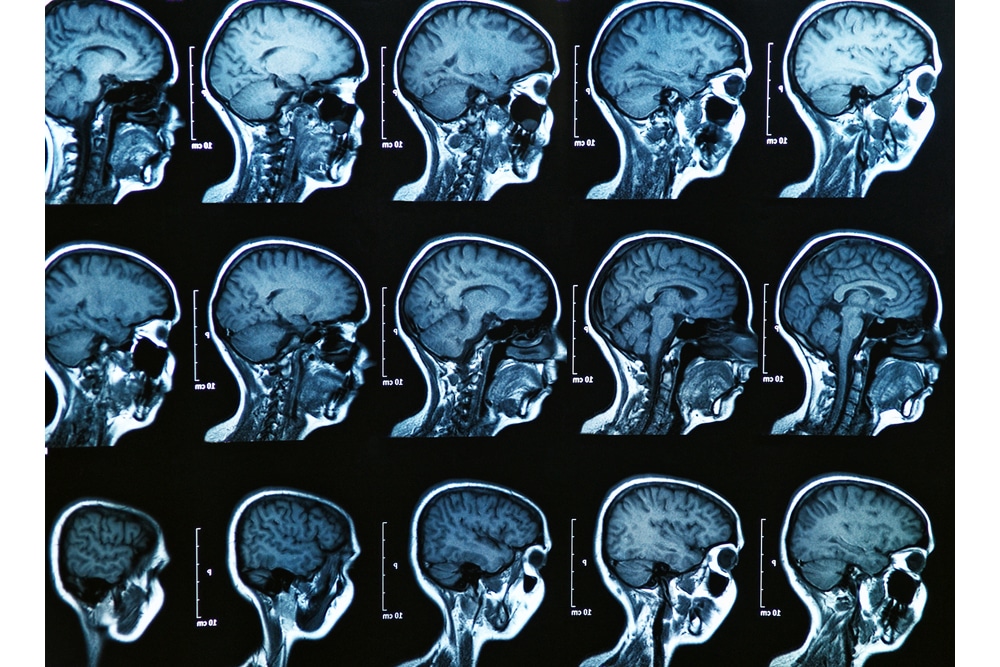

Ein medizinisches Fachjournal und führende Medien in Deutschland wie auch die New York Times berichteten im Oktober, dass Krebsforscher aus Amsterdam ein neues Organ gefunden hätten. Ein bislang unbekanntes Paar an Speicheldrüsen an der sogenannten Tubenöffnung, dem Ende einer Verbindung der Paukenhöhle zum Nasen-Rachen-Raum, sei erstmals in positronen-emissionstomographischen (PET) Untersuchungen aufgefallen.

Rund 800 bis 1.000 dieser kleinen Drüsen sind im und um das Gewebe der Schleimhaut von Lippen, Mundhöhle, Nase und dem Mittelohr in unterschiedlicher Dichte verteilt. In der Regel sind sie nicht sichtbar und auch eine konventionelle Bildgebung ist nicht in der Lage, diese Drüsen darzustellen.